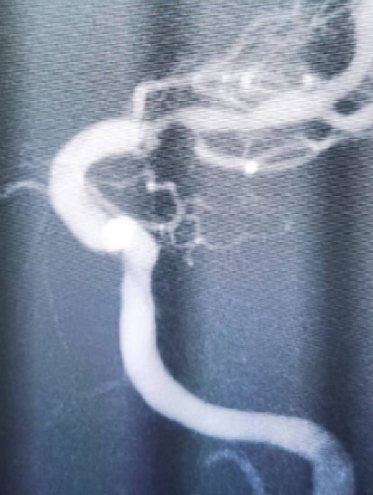

入院影像检查

导丝怎么扩【载药时代 球扩天下】NOVA DES®颅内药物洗脱支架在大脑中动脉重度狭窄中的应用两例!_https://www.jmylbn.com_新闻资讯_第5张

导丝怎么扩【载药时代 球扩天下】NOVA DES®颅内药物洗脱支架在大脑中动脉重度狭窄中的应用两例!_https://www.jmylbn.com_新闻资讯_第6张

重要影像结论DSA:左侧颈内动脉起始处重度狭窄、左侧大脑中动脉M1段偏心斑块伴重度狭窄。